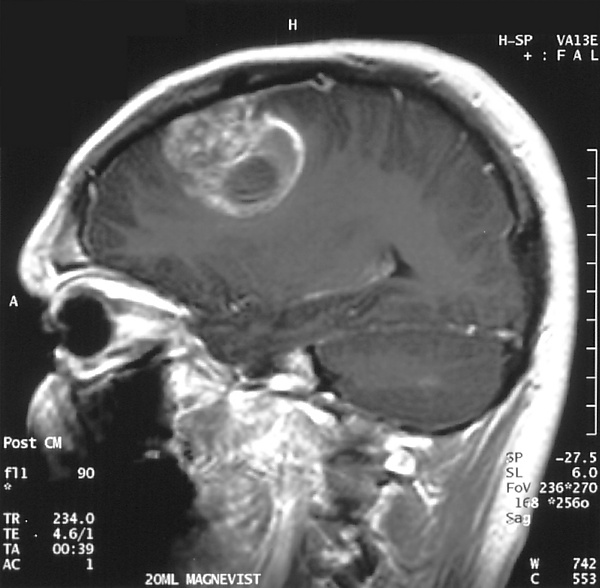

Сагиттальное контрастное МРТ-сканирование при глиобластоме у 15-летнего мальчика

При лечении может применяться химиотерапия, лучевая терапия и хирургическое лечение. «Золотым стандартом» в первой линии лечения пациентов с глиобластомами является максимально возможное удаление опухоли с последующим проведением комбинированной химиолучевой терапии с темозоломидом и последующей адъювантной химиотерапией темозоломидом в течение года.